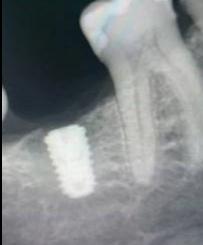

На первом фото «До» — пустота. Отсутствует первый нижний моляр, шестой зуб, который несёт основную жевательную нагрузку. Пациент уже привык жевать на одну сторону, соседи начали потихоньку смещаться, антагонист сверху потерял опору и медленно полз вниз. Классическая картина: один зуб ушёл — и вся система поехала.

Дальше был план, диагностика, расчёты. И момент, который вы видите на втором снимке, — рентген с установленным имплантом. Это не просто "винтик вкрутили". Это хирургическая точность до миллиметра. Здесь важно всё: и ширина кости, и высота, и расположение относительно нижнелуночкового нерва, и угол наклона, чтобы будущая коронка встала идеально в прикус.